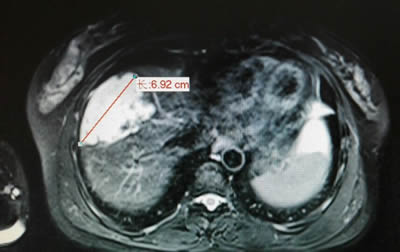

术前影像学发现右肝7×5cm的肝血管瘤 术前影像学发现左肝5×4cm的肝血管瘤